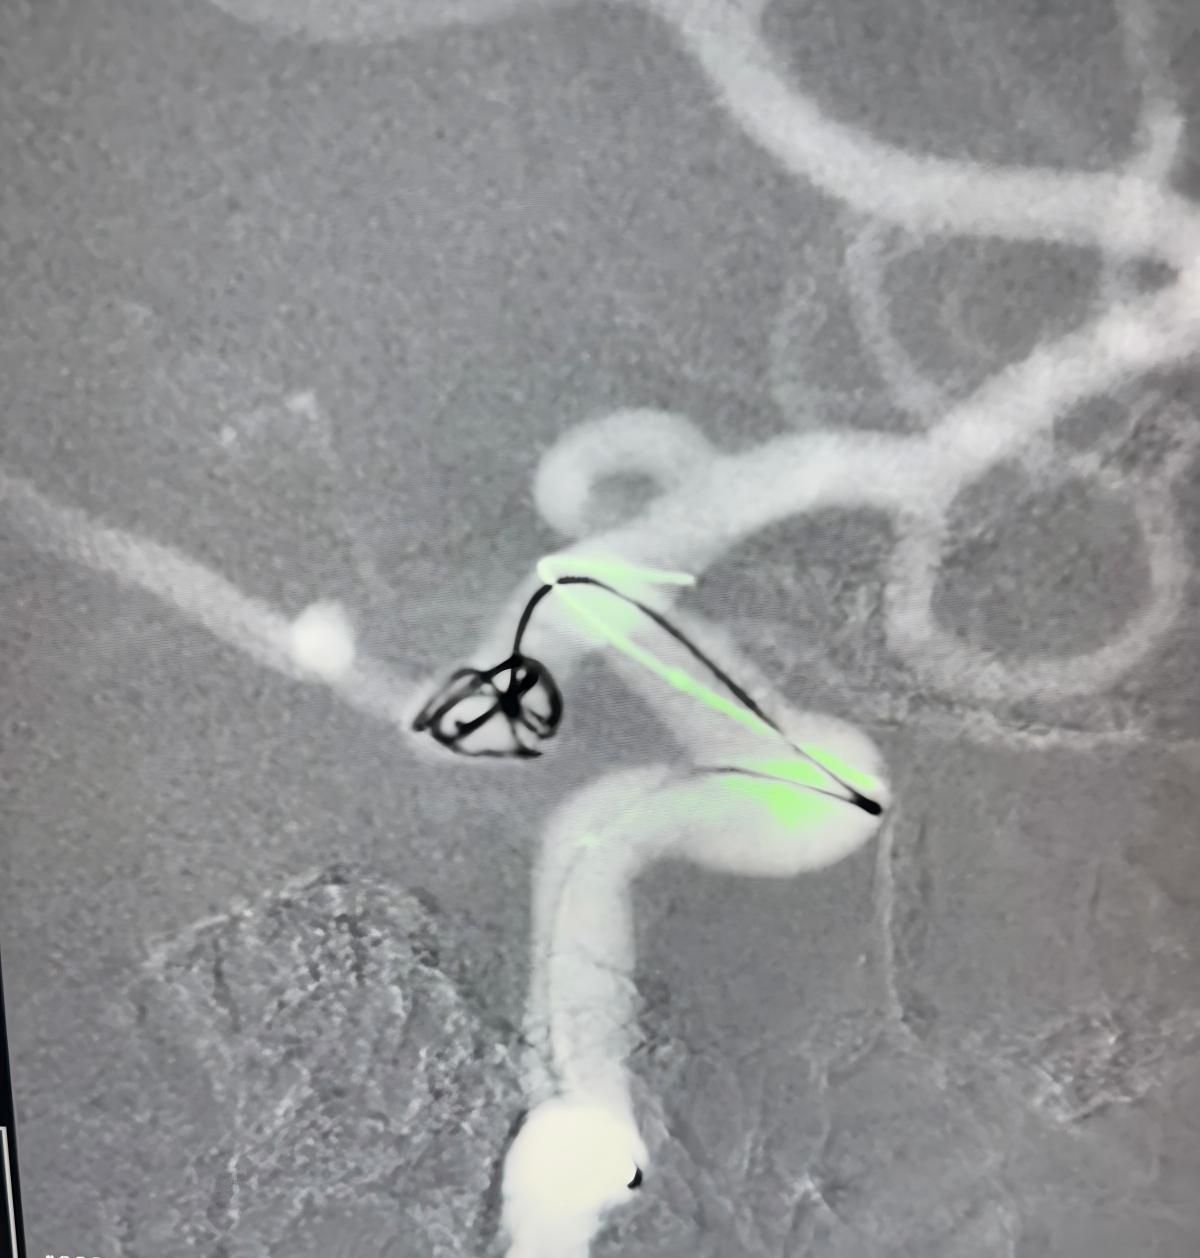

Мы рады поделиться недавней успешной процедурой в Клинике Альма Матер, Медельин, выполненной доктором Хорхе Мутисом.

Лечение использовалось Нува®Отвод потока (TJED-D 5,0-14), перденсатор®3D катушка и Frepass®Микрокатетер (TJMC18 Plus) для аневризмы задней сообщающихся артерий.

Доктор Мутис подчеркнул отличную видимость устройства и отметил, что извлечение было гладким. Он выразил большое удовлетворение в связи с окончательным результатом.